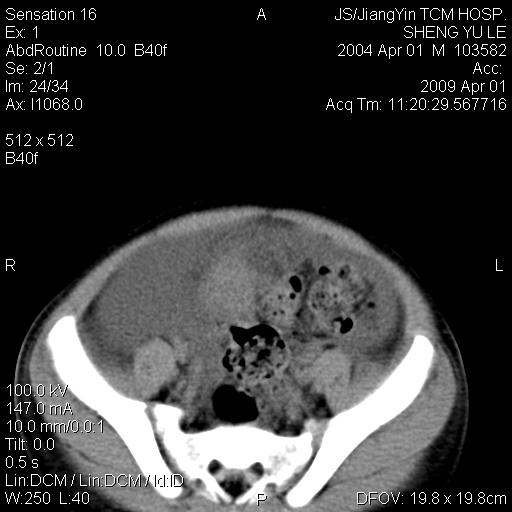

m,5岁。尿痛尿频数天。既往无病史。ct平扫腹盆腔积液。膀胱壁明显增厚。另可见心包增厚。wbc5万,骨髓穿等结果。请指教。

膀胱影像表现结合临床应该是急性膀胱炎症,但为什么有腹水呢?双肾输尿管无扩张,泌尿系压力应该不大不至于引起尿外渗,应该是腹膜感染引起的,但楼主没有提及相关症状,腹膜及膀胱结核?患者白细胞5万(结核不至于这么高啊),脾脏增大,是不是有白血病?进一步检查。。